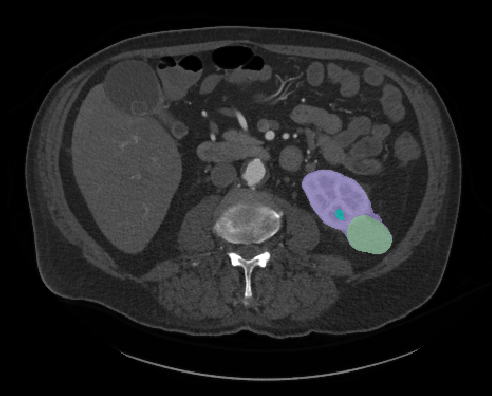

Heller is a PhD student conducting computer science research at University of Minnesota. His research focuses on using computer technology to enhance medical imaging, like a CT scan or an MRI. According to Heller, the magnified images will allow radiologists to quantify the type of tumor it is, saving time between a patient’s diagnoses and treatment.

“They will be able to measure a tumor mass, determine how big and rough they are, and whether they look distinct or blurry against the background. Medical professionals can use that information to choose the most effective treatment and predict a patient's outcome,” Heller explains.

The ARCS Scholar compiles information from the medical charts of real patients. He and other team members also work with radiologists to create hypothesis about how the appearance of a kidney tumor will relate to that patient’s outcome. Heller assigns numbers to each distinct feature the tumor. For instance, if a radiologist determines a tumor has a “hard boundary,” then Heller would quantify that description as anything over the number sixty.

(Courtesy: Nick Heller)

“Then we can turn those numbers into a computer code. If we can automate the code with images and equipment, a radiologist can just hit a button and receive information on the tumor, rather than looking at the image and making a judgement call,” Heller states.